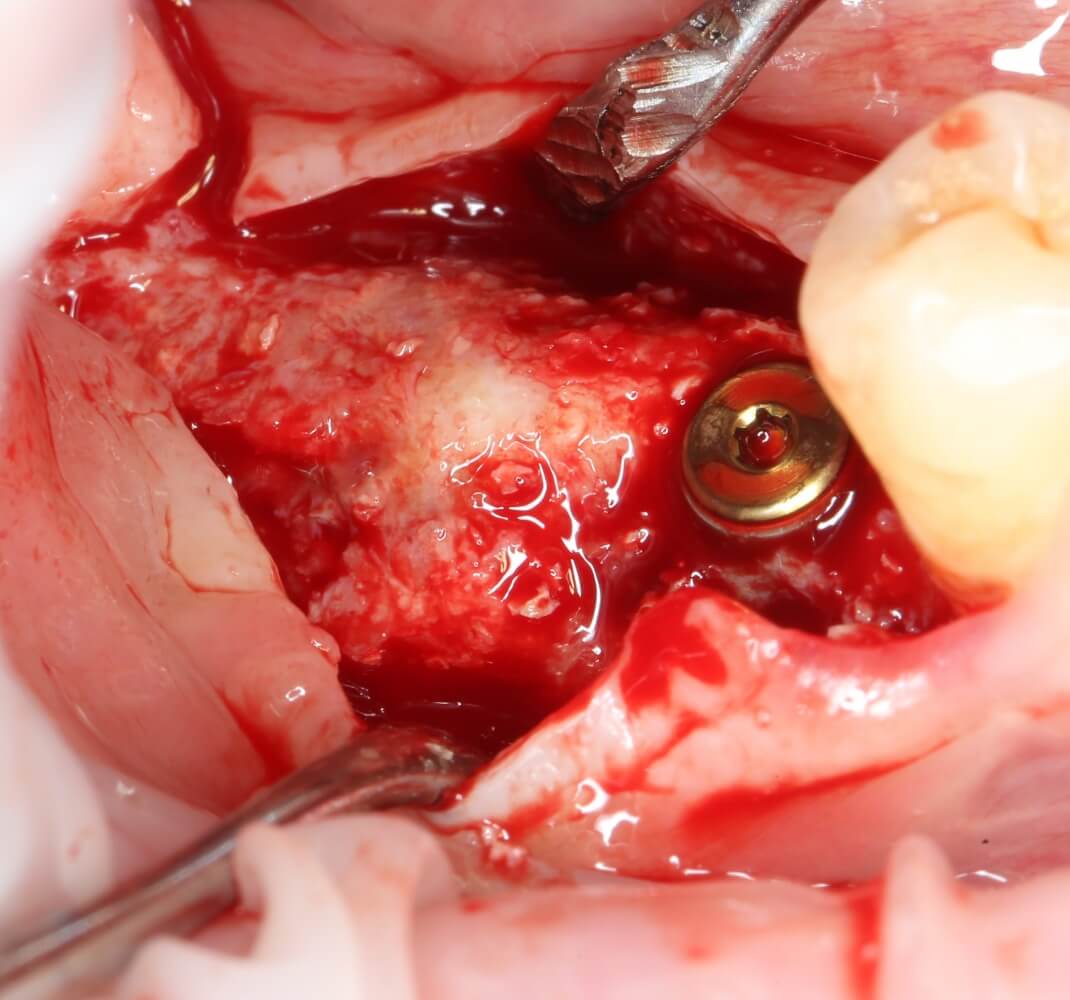

Изоляция области аутографта и имплантатов барьерной мембраной.

Перекрывать костный блок барьерной мембраной или оставить так? По этому вопросу есть много мнений. Между тем, в публикации по методике есть ясное показание, когда это требуется.

Конкретно в этом клиническом случае между костным аутотрансплантатом, ложем и имплантатами есть пустое пространство. Если его не изолировать от мягких тканей, они прорастут и осложнят интеграцию аутографта. Поэтому я решил перекрыть костный блок барьерной мембраной, пусть это делает хирургическую операцию немного дороже.

На этом этапе есть несколько нюансов, о которых я хочу рассказать отдельно.

— я использовал барьерную мембрану Geistlich Bio-Gide, которая имеет две разные поверхности: с одной стороны она рыхлая «адгезивная», с другой — гладкая и прочная. Как укладывать — на результат не влияет, но в плане удобства рыхлую поверхность мы «приклеиваем» к тому, на чем требуется барьерную мембрану удержать. В данном случае хотелось бы удержать её на костной поверхности — следовательно, мы укладываем её рыхлой поверхностью к кости.

— много лет мы используем антибиотики для интраоперационной профилактики инфекционно-воспалительных осложнений. Уже в то время мы пришли к выводу, что удобнее всего — порошки антибактериальных препаратов для приготовления раствором: дешевые, стерильные, в удобной упаковке. Прямо в виде порошка их можно добавлять в графт, растворы для ирригации, либо использовать так, как показано на фото. Еще мы используем порошок антибиотика для изготовления пасты, которой обрабатываем имплантаты в процессе ревизии или при лечении периимплантита. Это удобнее и эффективнее, чем интраоперационное использование жидких форм антибактериальных препаратов.

— ты знаешь, что барьерная мембрана может выполнять две функции, каркасную и изолирующую. Первая функция требует обязательной фиксации и натяжения, вторая — нет. В нашем случае «каркасом» регенерата является костный блок, а барьерная мембрана нужна только для изоляции. Поэтому она не требует натяжения и фиксации пинами.

После я внимательно проверил, что костный блок и имплантаты полностью перекрыты. Теперь рану можно ушивать.